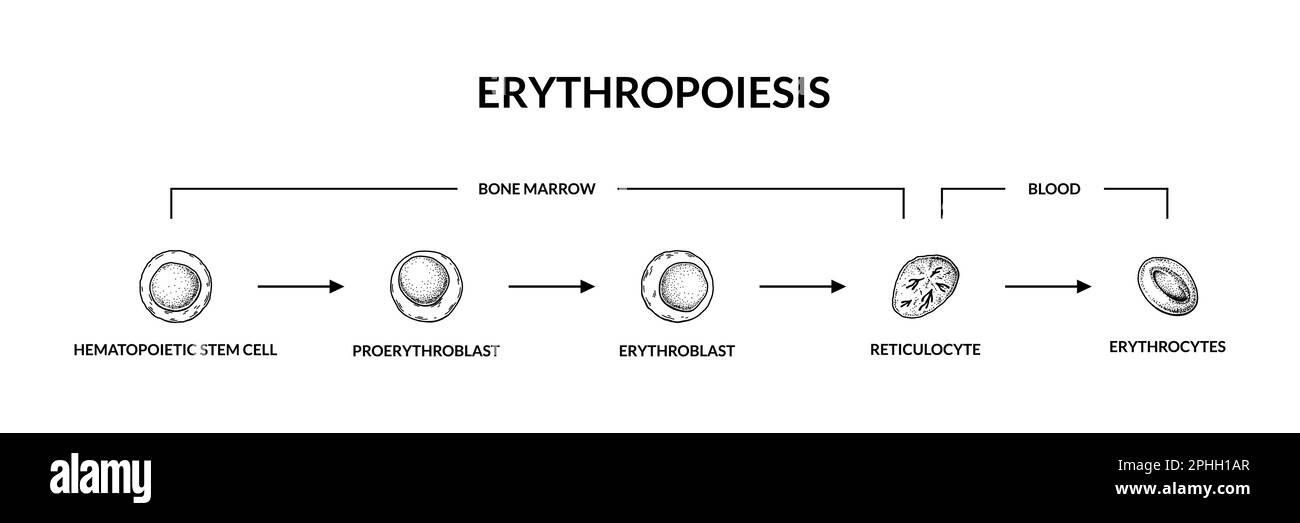

Développement des globules rouges. Érythropoïèse. Illustration de vecteur de microbiologie scientifique dans un style d'esquisse Illustration de Vecteurhttps://www.alamyimages.fr/image-license-details/?v=1https://www.alamyimages.fr/developpement-des-globules-rouges-erythropoiese-illustration-de-vecteur-de-microbiologie-scientifique-dans-un-style-d-esquisse-image544344831.html

Développement des globules rouges. Érythropoïèse. Illustration de vecteur de microbiologie scientifique dans un style d'esquisse Illustration de Vecteurhttps://www.alamyimages.fr/image-license-details/?v=1https://www.alamyimages.fr/developpement-des-globules-rouges-erythropoiese-illustration-de-vecteur-de-microbiologie-scientifique-dans-un-style-d-esquisse-image544344831.htmlRF2PHH1AR–Développement des globules rouges. Érythropoïèse. Illustration de vecteur de microbiologie scientifique dans un style d'esquisse